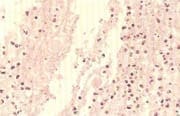

Figura No 2 Microfotografía de úlcera amibiana con

trofozoítos: figuras redondeadas centrales con halo

claro y tejido acelular a su alrededor.

La mucosa de esta víscera muestra zonas de ulceras profundas con trofozoítos de amebas (figura No 2) alternas con áreas de hemorragia de la mucosa superficial y de la submucosa, vasodilatación, y presencia de polinucleares linfocitos y plasmocitos en todo el espesor de la pared con compromiso de los plexos nerviosos (figura No 3). Los riñones tienen cambios de necrosis cortical aguda.